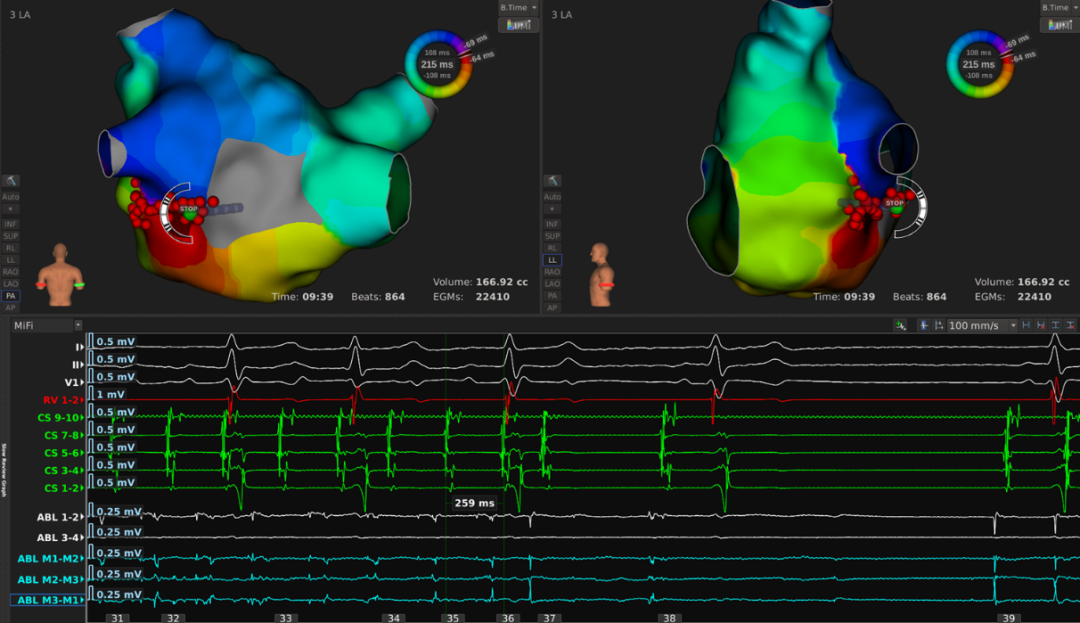

患者至手术室时心率为147次每分钟,常规消毒铺巾后,放置冠状窦十级导管,心室四极导管和Orion标测导管。在波士顿科学Rhythmia连续自动标测系统的指导下,利用Orion高密度标测导管快速标测右房。耗时7分43秒,获取有效标测点9611个(Projection Distance=2mm)。激动标测提示:冠状窦口最早激动,CL未标满,且最早点激动时间晚于CS5-6的A波,提示该房速可能来源于左房。遂穿刺房间隔至左房。利用Orion高密度标测导管快速标测左房。耗时9分钟39秒,获取有效标测点22410个(Projection Distance=2mm)。激动标测提示:左房游离壁有条阻滞线,左房后壁偏下位置有块疤痕区,房速机制绕左房后壁疤痕和右下肺静脉的逆钟向大折返。

AFL Mechanism